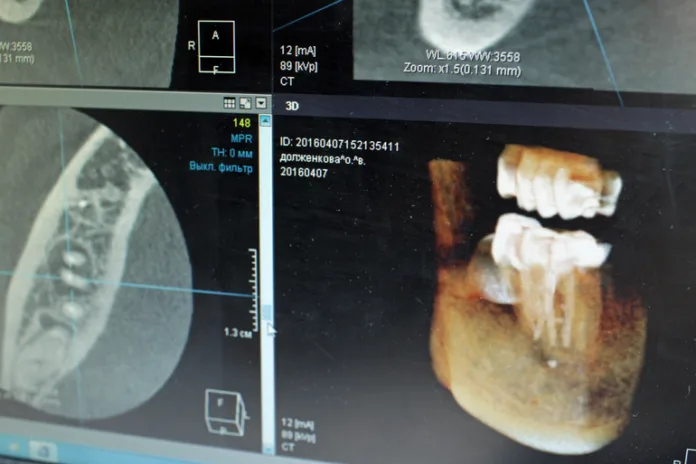

По словам парламентария, искусственный интеллект уже сейчас активно используется при анализе рентгеновских снимков, проведении скрининговых исследований и обработке данных томографии. Однако она подчеркнула, что окончательный диагноз может ставить только квалифицированный врач.